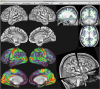

Description:Functional connectivity viewing in Workbench